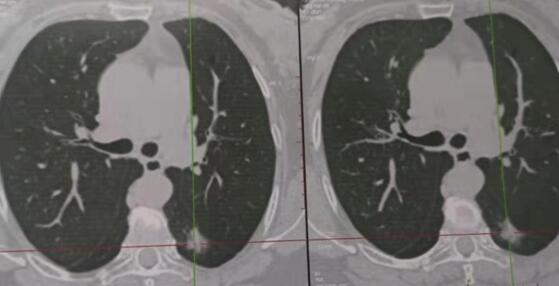

近日,肿瘤胸外科成功完成三例胸腔镜下肺癌根治术。三名患者均系体检时发现肺部直径约15mm左右结节,行多项检查均考虑恶性不除外,但无法确诊,来我科就诊,根据患者病情,苗满园主任带领科室医师经研究讨论,在全麻下行胸腔镜下肺楔形切除送术中冰冻病理确诊为肺癌,并行胸腔镜下肺癌根治术,手术顺利完成,时间2小时。科室全程引入加速康复理念,少插管,早拔管,患者均快速、顺利康复出院。该治疗的成功引入,使我院肿瘤胸外科胸腔镜手术水平跃上新台阶。